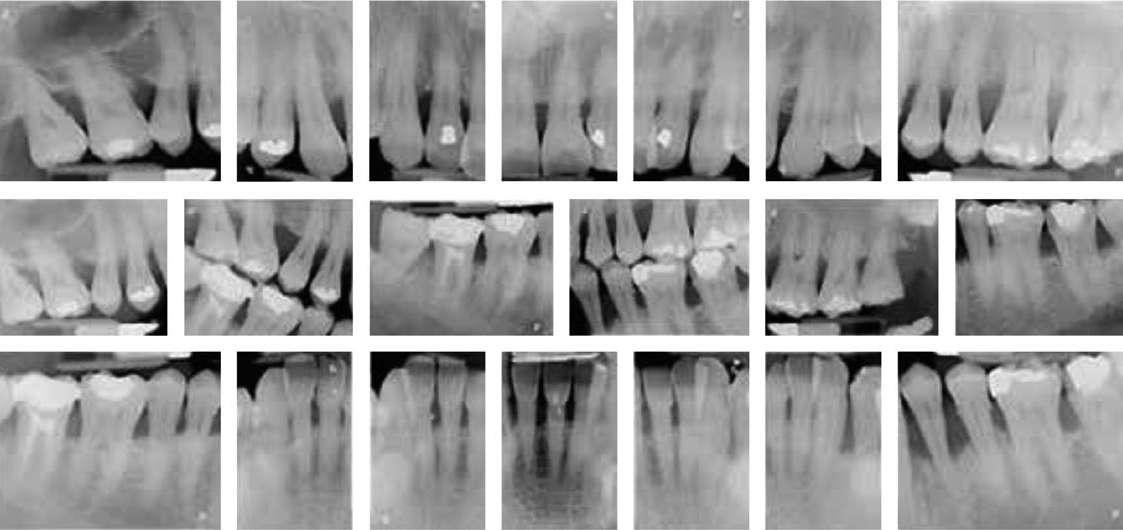

El examen radiográfico (Figuras 3 y 4) reveló, además de una pérdida ósea horizontal generalizada, la presencia de defectos intraóseos a nivel de 1.2 y 3.3. Según el algoritmo de Tonetti y Sanz (2019), al no presentar registros previos se determinó el grado por medio de la evidencia indirecta, para lo cual se tomó el diente con mayor afectación periodontal, tratándose del 3.4, y valorando la pérdida ósea en relación con la edad, siendo superior a 1, estableciéndose un grado C.

Se recolectaron muestras microbiológicas subgingivales con puntas de papel de las bolsas con mayor profundidad y sangrado de cada cuadrante. Los recuentos totales de anaerobios del paciente fueron de 1,18 x 106, con una proporción de Porphyromonas gingivalis del 0,85 % y de Tannerella forsythia del 3,39 % sobre el total de la flora subgingival. Tras la recopilación de datos clínicos y radiográficos, el paciente fue diagnosticado de periodontitis estadio IV generalizado grado C, tipo II al tratarse de un paciente con migración dental patológica, caracterizada por extrusiones, desplazamiento y abanicamiento dentario, que es susceptible de ser corregida mediante ortodoncia de acuerdo con la Clasificación de Enfermedades y Condiciones Periodontales y Periimplantarias de 2018 (Caton y cols. 2018; Herrera y cols. 2022; Papapanou y cols. 2018).

Figura 4. Serie periapical completa.